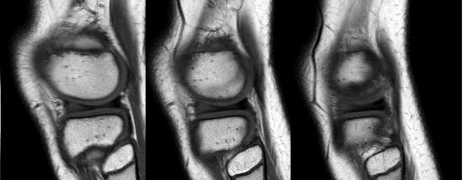

Stoler et al.suggéré 3 grades de ménisque (Figure 4)

Grade 1 : Ménisque nodulaire en hypersignal retenu à la surface du ménisque ;

Grade 2 : Ménisque linéaire à signal élevé retenu sur la surface du ménisque ;

Grade 3 : L'hypersignal s'étend à une surface articulaire du ménisque.

Figure 4 Échelle de Stoller.a : Grade 1 : Un ou plusieurs sites d'hypersignal nodulaire intermédiaire associés à la surface articulaire du ménisque ;b : Grade 2 : Hypersignal linéaire intermédiaire sur la surface articulaire du ménisque ;c : Grade 3 : Hypersignal intermédiaire linéaire s'étendant jusqu'à une surface articulaire du ménisque.

Bien que la distinction entre les grades 2 et 3 soit modeste, elle distingue l'hypersignal intraméniscal dégénératif (Figure 5) des véritables fissures.Cette distinction entre un ménisque dégénéré et déchiré n'est pas toujours simple, et il existe de nombreuses sources d'erreur dues à l'apparition d'excédents ou de manques.